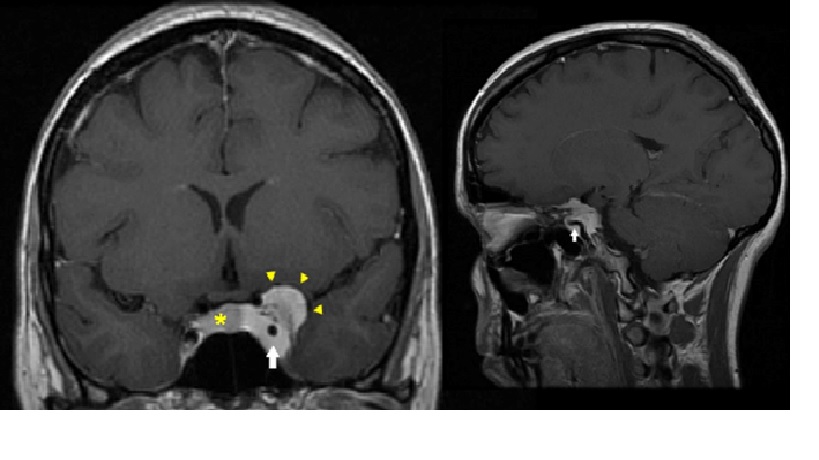

Khối u xoang hang

MRI T1W sau cản quang, coronal (left) và sagittal (right, scaled down). Lưu ý sự tăng cường đồng nhất của khối u chiếm và nhô ra qua thành bên của xoang hang trái. Đầu mũi tên màu vàng cho thấy một phần nhỏ ngoài hang. Động mạch cảnh trong bị hẹp và di lệch được bao bọc (mũi tên trắng). Tuyến yên bị đẩy sang phải (dấu sao vàng).